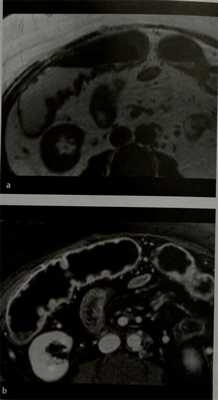

а, b Язвенный колит. МРТ.

a) Небольшое утолщение стенки в восходящем и поперечном отделах ободочной кишки и локальное псевдополипоидное утолщение стенки кишки; b) Стенка кишки и псевдополипоидные изменения накапливают контраст.

Что покажут снимки МРТ брюшной полости при неспецифическом язвенном колите

- Только дополнительный метод исследования;

- Стенка кишки утолщена;

- На Т2-взвешенных изображениях в режиме подавления сигнала от жировой ткани острое воспаление (отек) визуализируется хорошо, выражаясь интенсивным сигналом от кишечной стенки и окружающих ее тканей;

- Хороший метод визуализации стенозов.